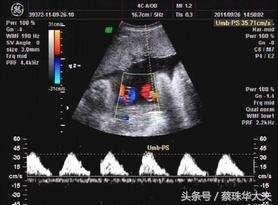

胎儿脐动脉血流是胎儿胎盘循环血流动力学的无创性监测手段。

胎儿脐动脉多普勒指数间接反映了胎儿血液流向胎盘的阻抗情况,其异常与胎儿胎盘血管的病理性异常相关,且与胎儿缺氧、酸中毒和不良围产儿结局明显相关。

在妊娠28周后,S/D>3.0或者RI>0.6是胎儿不良结局高风险的最佳阈值;而在妊娠28周前,其应用价值尚待进一步研究。

脐动脉多普勒血流频谱波形中,最重要的诊断性指标是舒张末期流速。如果发现脐动脉舒张末期血流消失(AEDV),高度提示胎儿状况极其危险,一旦孕周≥34周,需积极终止妊娠;如果出现脐动脉舒张末期血流反向(REDV),其预示着胎儿预后更差,且可以看作是胎儿濒死的征兆,只要孕周≥28周,可考虑尽快终止妊娠抢救胎儿。